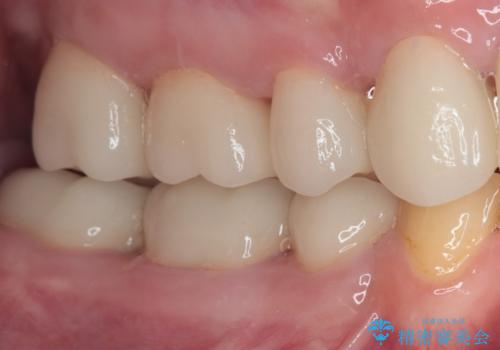

矯正治療終了後に、残った歯をオールセラミッククラウンにて補綴治療を行うこととしました。

途中来院が困難な時期があったり、歯周外科処置を行って治癒を待ったりと、治療期間は長くなりましたが、初診時とは比べものにならないくらいきれいに仕上げることができました。